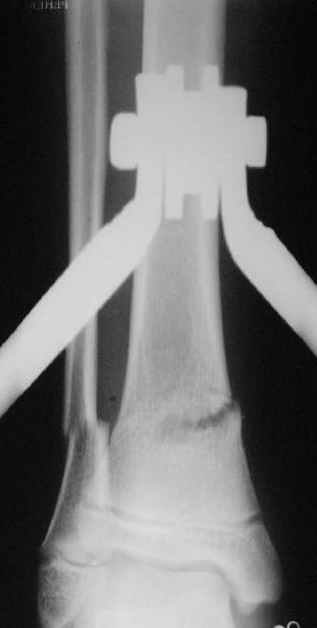

Так как речь зашла непосредственно о травме, см этапные

снимки. Как все было

Вытяжение

|

Фиксация

в гипсе